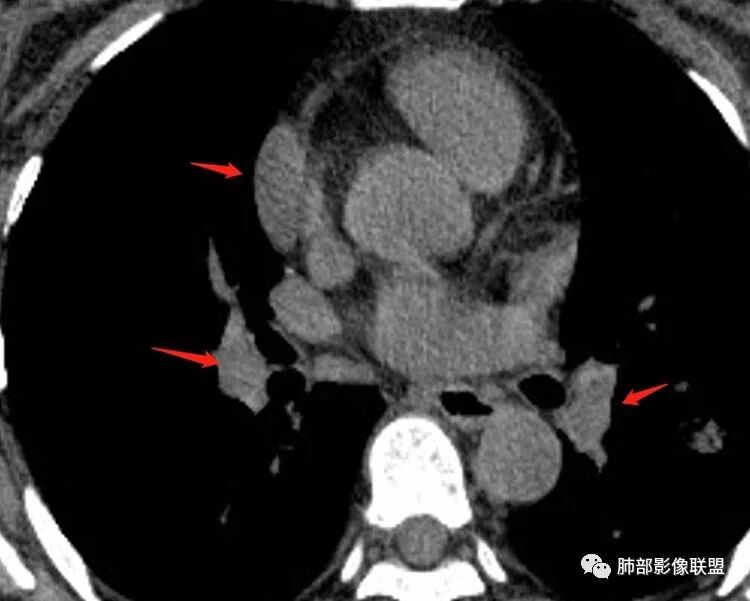

这些好像也大,会不会是肿大淋巴结

南边:有边界清楚GGO吗张玉:有南边:有就好办边界清楚MGGO,分叶、胸膜凹陷

下面这个如何考虑?

那么小不转移吧,另外一个结节?

不是转移。毛玻璃,原发可能,需要随访

边界清GGO?随访是个好主意

会不会是肺内淋巴结?

一般临床处理是立刻开左边的,在胸膜旁的很好定位。右边随访

肺内淋巴结是实性的

淋巴结一般实性